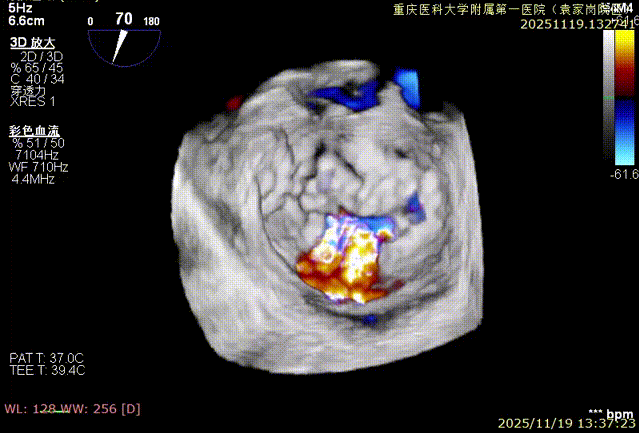

术前食道超声评估:三尖瓣重度反流,FTR6+,反流位于前隔、中央,后隔。瓣叶粘液样变性,后隔可见4.6mm gap。

对患者三尖瓣瓣环和右冠跟瓣环距离等完成多维度评估后,充分结合其病变特点与解剖结构细节,确立以双夹K-Clip®植入为核心的精准治疗方案。手术操作中,16T型号K-Clip®植入三尖瓣后隔瓣环偏隔瓣处,16T型号K-Clip®则植入前后交界处。该术式通过双点定位植入的精准操作,可有效缩减三尖瓣瓣环直径、提升瓣叶对合效能,从解剖学层面直接纠正三尖瓣反流,为患者术后顺利恢复提供关键的结构支撑。

手术效果评估

反流评估:术前6+下降至1+